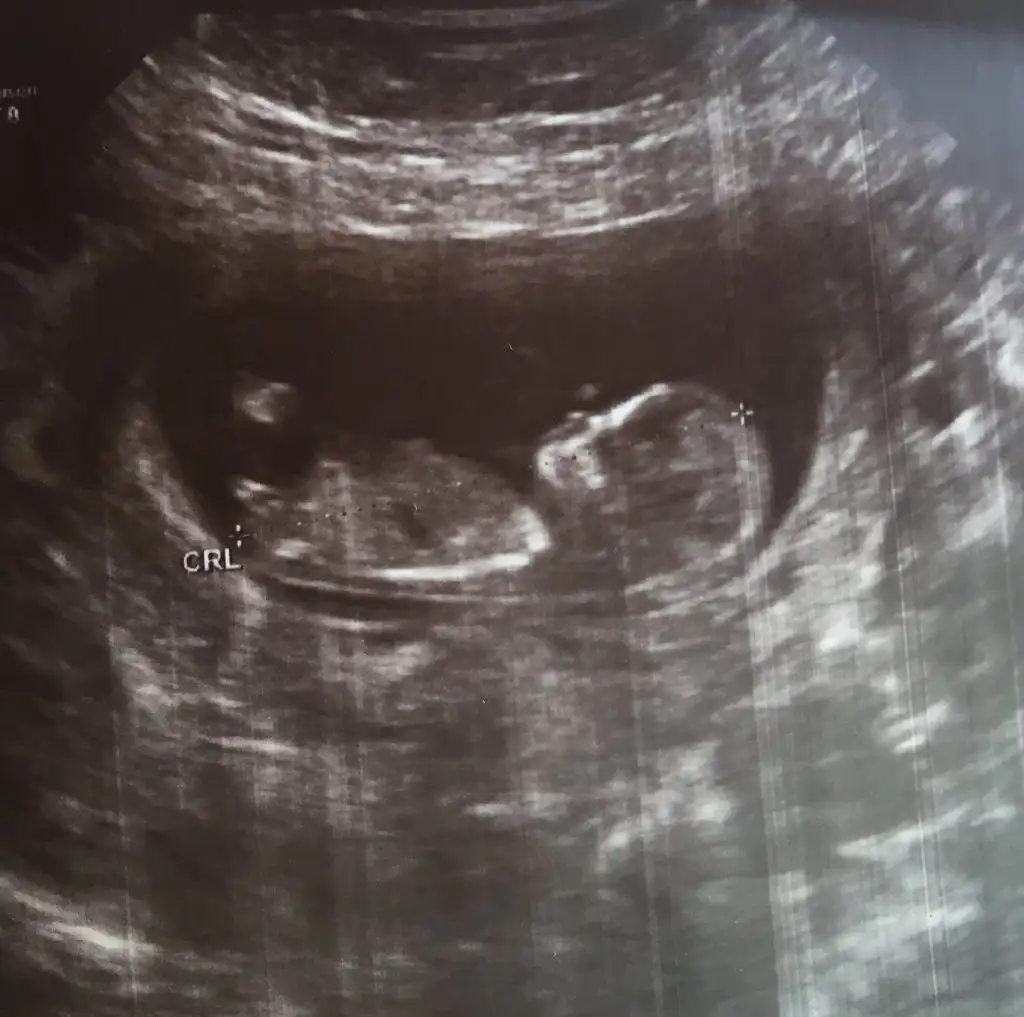

Kıza benzettim ben canımKızlar nasipse bende mart annesi olacağım. Son adet tarihime göre 12+0 haftalık ama bugün ikili tarama için gittim 12+4 haftalık çıktı bunlarda görüntüleri. Sizce cinsiyeti nedir nub anlayan var mı

Pek emin olamadım ama erkek gibi geldi, sağlıkla gelsin inşallahKızlar nasipse bende mart annesi olacağım. Son adet tarihime göre 12+0 haftalık ama bugün ikili tarama için gittim 12+4 haftalık çıktı bunlarda görüntüleri. Sizce cinsiyeti nedir nub anlayan var mı